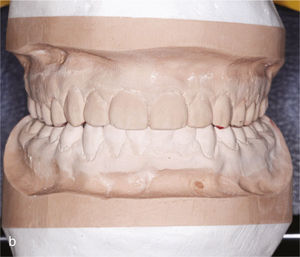

El paciente se presentó en nuestro centro con el siguiente cuadro: dentición permanente con proinclinación de dientes anteriores y desviación de la línea media, diente 53 persistente, dientes 13 y 23 elevados y desplazados hacia vestibular, curva de Spee marcada con extrusión del sector anteroinferior, dientes rotados y apiñados en maxilar y mandíbula, clase II de Angle con un resalte de 4mm y sobremordida de 0mm, además de ausencia de guía canina (figs. 13a a 13c y 14a a 14e).

El plan de tratamiento incluyó el establecimiento de una clase I de Angle con sobremordida horizontal y vertical fisiológicas mediante la distalización del sector posterosuperior, con corrección de los caninos superiores y aseguramiento de una guía canina. Las arcadas se dotaron además de una apariencia armoniosa eliminando la giroversión y los apiñamientos mediante la reducción del esmalte interproximal y el ajuste de las líneas medias. El paciente optó por un tratamiento con el sistema Invisalign alternativo a la aparatología fija con brackets. Se colocó un atache rectangular vertical en los dientes 13 y 23 y, en el curso del tratamiento, también en los dientes anterosuperiores y en el diente 43. Además durante todo el tratamiento el paciente llevó elásticos de clase II en ambos lados, del diente 14 al diente 46 y del diente 24 al diente 36 para obtener el anclaje necesario durante la distalización. La figura 15 muestra la situación intraoral de un caso similar con brackets en los dientes 13 y 46. En la zona de los brackets se acortó el alineador. Además de los alineadores se utilizaron elásticos de clase II del diente 13 al diente 46.

La situación intraoral después de finalizar el tratamiento (figs. 16a a 16e) muestra, como lo hacen los modelos montados en relación céntrica (figs. 17a a 17e), una clase I de Angle con relación intermaxilar anterior fisiológica y una guía canina asegurada. En la radiografía panorámica final no se observan signos patológicos; se indicó la extracción de los terceros molares inferiores (fig. 18). El paciente utilizó férulas de Imprelon durante la noche como sistema de retención (Scheu-Dental, Iserlohn).